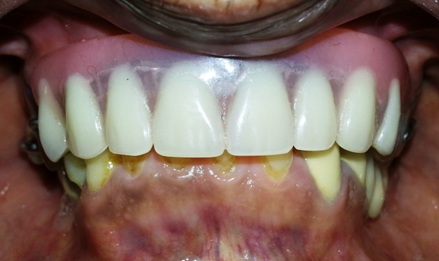

The denture base acrylic replicated the lost natural soft-tissue architecture and permitted placement of appropriate sized teeth. The final result provided a stable and functional RPD with a highly aesthetic appearance for the patient [Table/Fig-8].

Intraoral facial view of the implant supported RPD